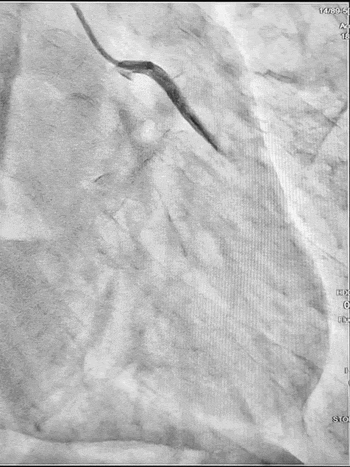

Ургентна коронароангіографія - LCA- помірно виражена, без явищ стенозування на всьому протязі. Відмічаються поодинокі колатеральні гілки в дистальний сегмент RCA. RCA- помірно виражена. Відмічається дисекція інтими в ділянці гирла. В проксимальному сегменті - гілок не виявлено. В середньому сегменті - оклюзована за рахунок великої кількості тромботичних мас.

Стентування визнано недоцільним, обрану консервативну тактику ведення пацієнта. Враховуючи стабільну гемодинаміку тимчасову ЕКС не проводили, але тримали стимулятор напоготові.

Яка причина ІМ у даного хворого? Цей випадок схожий на ось цей, коли у молодого пацієнта без кардіологічного анамнезу оклюзія коронарної артерії виникла на фоні екстремальних навантажень (змагання з пауерліфтингу). Ми не знаємо стан артерії нашого сьогоднішнього пацієнта до події: можливо, в проксимальному відділі ПКА вже була присутня гемодинамічно незначуща атеросклеротична бляшка, яка і виявилась “слабким місцем”, що при підвищенні тиску в момент наванатаження розірвалась і призвела до відшарування інтими [1,2,3].